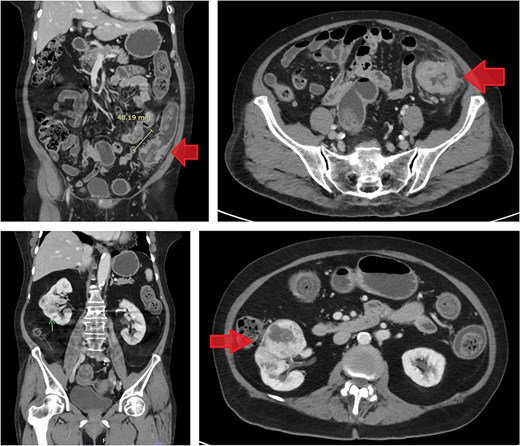

Histopathological specimens of the kidney revealed clear cell RCC (ccRCC) (Fig. 5), measuring 4.0 × 4.0 × 3.8 cm with a histologic grade of G2. The tumor growth was limited to the kidney, with all margins negative for invasive carcinoma. Tumor necrosis was present at 10%. Lymphovascular invasion was present. This case of RCC was staged as T1aN0M0 according to the TNM classification [8]. The sigmoid colon mass analysis revealed low-budding, well-differentiated adenocarcinoma, size 6.5 cm, with submucosal invasion (T1). There is no lymphovascular or perineural invasion. The margin was negative for both proximal and distal mesenteric margins. The remaining tissue examination revealed a tubular adenoma with focal high-grade dysplasia. There were negative results for metastatic carcinoma in all 12 lymph nodes from the specimen. In this case, the TNM staging for the sigmoid colon carcinoma was determined to be T1N0M0 [9].

The histological section of RCC shows clear cytoplasm and cellular morphology consistent with clear cell RCC.